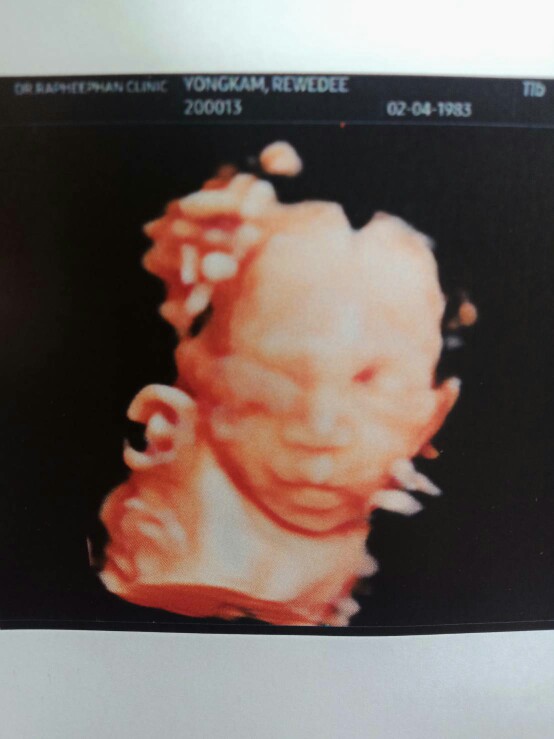

บ้านนี้ 31w ละคะ กำหนดคลอด 6 สิงหา น้อง ผญ #พึ่งไปซาว4มิติมา #เห้นน้องชัดมากอิแม่ปลื้ม ?